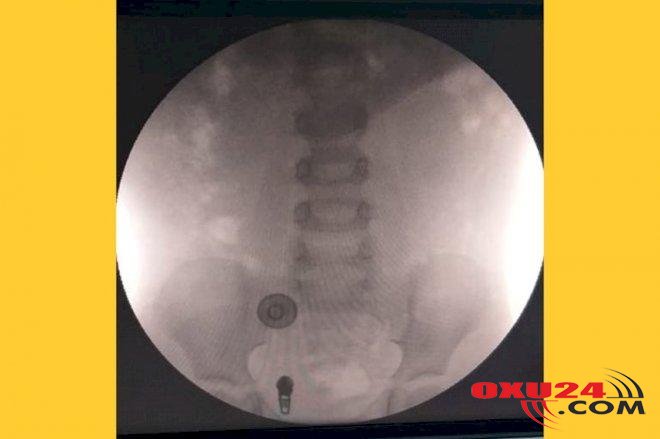

\"Yoxlamalardan sonra əməliyyat qərarı verildi. Əməliyyat üçün 1 saylı Kliniki Tibbi Mərkəzin cərrahı Allahverdi Musayevə müaricət etdik. Cərrah ilkin yoxlamaların, USM-nin nəticələrini bəyənməyərək yenidən yoxlamalar, analizlər apardı. Nəticədə cərrah əməliyyata qərar verdi və bizə bildirdi ki, böyrək çıxarılmayacaq, \"stend\" qoyulacaq. Bunun gələcəkdə hansı problemləri yaradacağını soruşduq. Allahverdi Musayev bizə dedi ki, 30 yaşına qədər heç bir problem olmayacaq. 2018-ci ilin 9 martında əməliyyat oldu, amma bir neçə aydan sonra problemlər ortaya çıxdı. Yenidən başqa həkimə müraciət etdik. Yoxlama nəticəsində məlum oldu ki, Allahverdi Musayev əməliyyat adı altında uşağı ancaq sünnət edib. Böyrəklə bağlı heç bir iş görülməyib. Ancaq əməliyyat izi qoyub. USM yoxlamalarından məlum oldu ki, Allahverdi Musayev \"stend\" qoymayıb. Baxmayaraq ki, əməliyyat buna görə olub və məhz \"stend\"ə görə biz vəsait ödəmişik. Ümumilikdə isə Allahverdi Musayevə 1900 manat pul vermişik. Şəxsən öz əlimlə bu pulu həkimin özümə vermişəm. 1900 manatdan 850 manatı \"stendə\", 50 manatı isə sünnətə görə ödənilib. 1000 manat isə həkimə əməliyyat pulu kimi verilib. Bundan əlavə isə analizlərə və digər prosedurlara görə xərcimiz çıxıb\". Şikayətçi 4 yaşlı Cavidanın artıq ikinci əməliyyat keçirdiyini deyib: \"Artıq ikinci əməliyyat da baş tutub. İkinci əməliyyatı isə Akademik M.C.Cavadzadə adına Respublika Klinik Uroloji Xəstəxanasının cərrahı Eldar Hüseynov edib. Əməliyyat bu ayının 23-də olub. Yoxlamalardan sonra Cavidanın böyrəyinin artıq inkişafdan qaldığını və çıxarılmasının məcbur olduğunu dedilər. Nəticədə Cavidanın bir böyrəyi çıxarıldı. Allahverdi Musayevin səhvimi, səhlənkarlığımı ucbatından 4 yaşlı balamız iki dəfə bıçaq altına düşdü\". Şikayətçi Gülsüm Şükürova Allahverdi Musayevdən onlara dəymiş zərərin ödənilməsini istəyir: \"Allahverdi Musayev bizə maddi və daha çox mənəvi zərər vurub. İkinci əməliyyatın stressini, xərcini də nəzərə alsaq, bizə dəymiş zərərin nə qədər böyük olduğunu görmək çətin deyil. Tələb edirik ki, Allahverdi Musayev bizə vurduğu zərəri ödəsin\". Məsələ ilə bağlı 1 saylı Kliniki Tibbi Mərkəzin  cərrahı Allahverdi Musayevlə əlaqə saxladıq. A.Musayev əvvəlcə belə bir xəstəsinin olmadığını, məlumatın yanlış verildiyini deyib. Bizə təqdim olunan sənədlərdə imzası olduğunu deyəndən sonra isə telefonu məşğula qoyaraq sualları cavablandırmaqdan yayınıb. \"\" \"\" \"\"